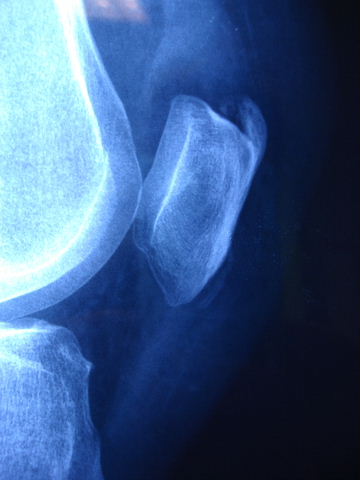

Prótesis completa de rodilla. Situación postquirúrgica.

Prótesis completa de rodilla. Situación postquirúrgica. Lateral.

Prótesis completa de rodilla.Lateral.

Prótesis completa de rodilla. Frontal.